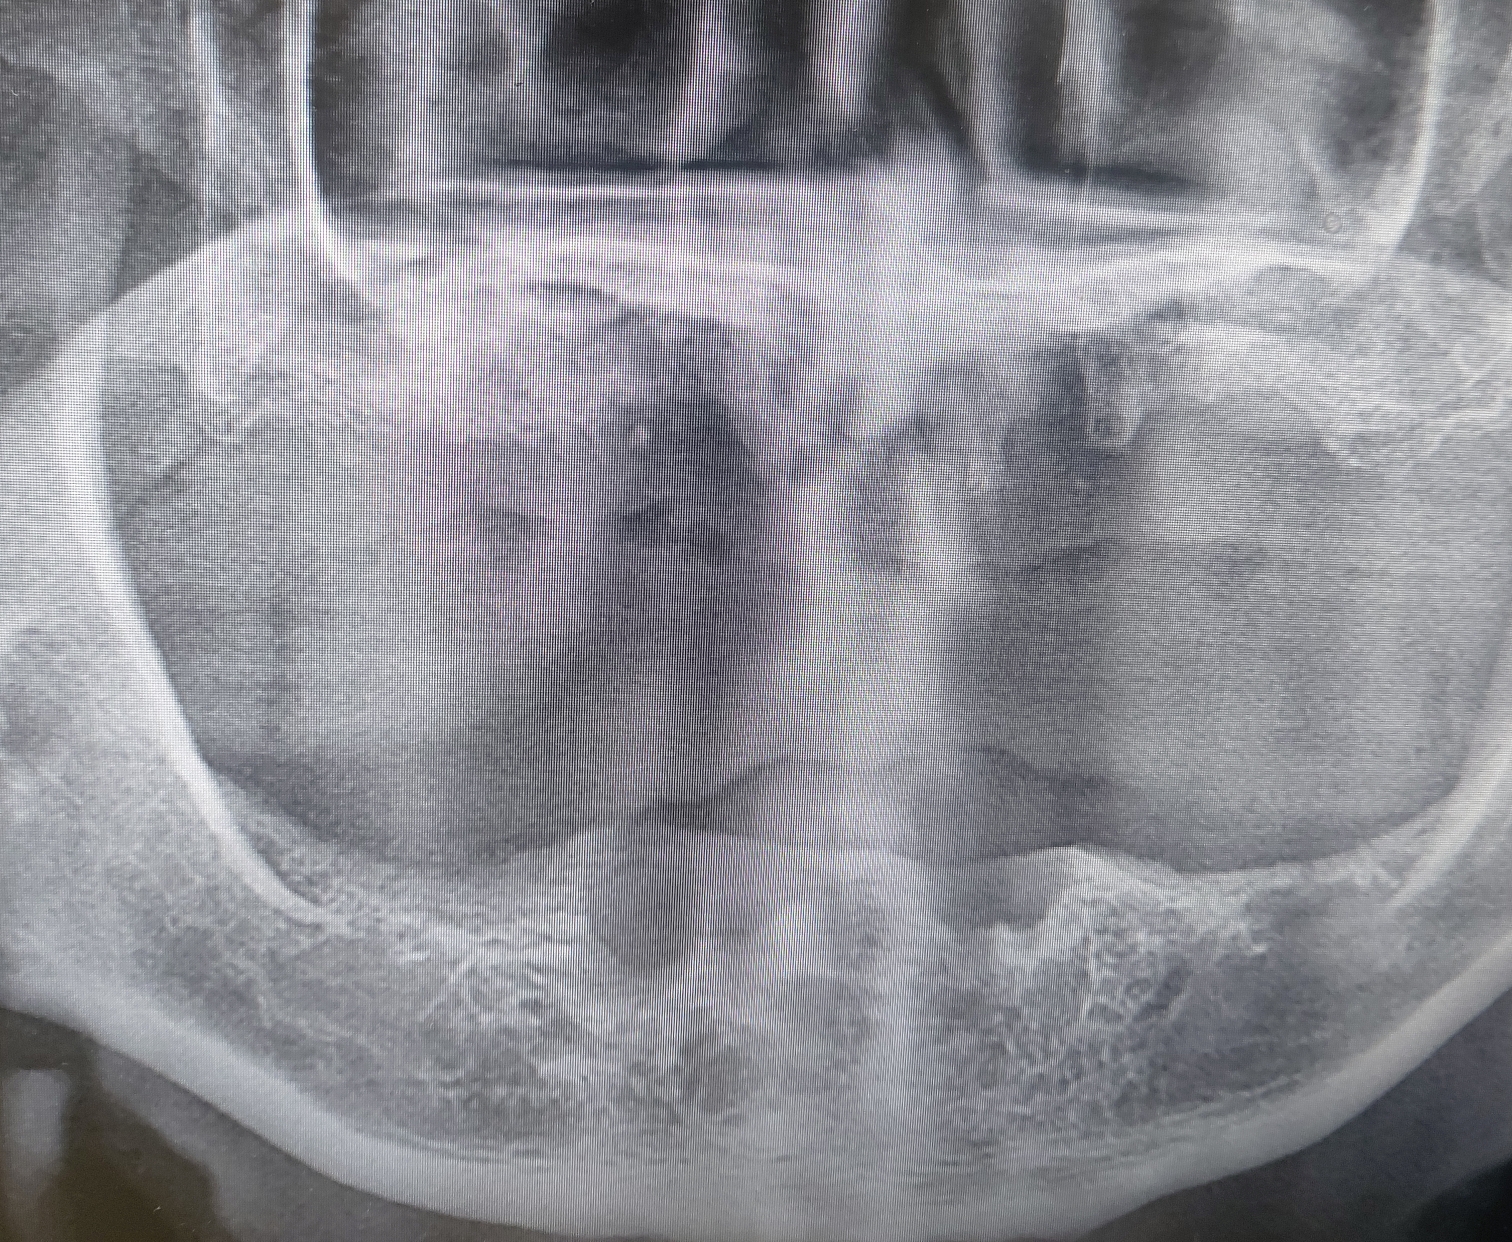

♧ 상악은 다시 양쪽 상악동 거상술시행후 지연식립

상악 2차 수술시 잘 유착된 임플란트를 보며 좋은결과를 예상했고 좋은 결과로 마무리 지었습니다.